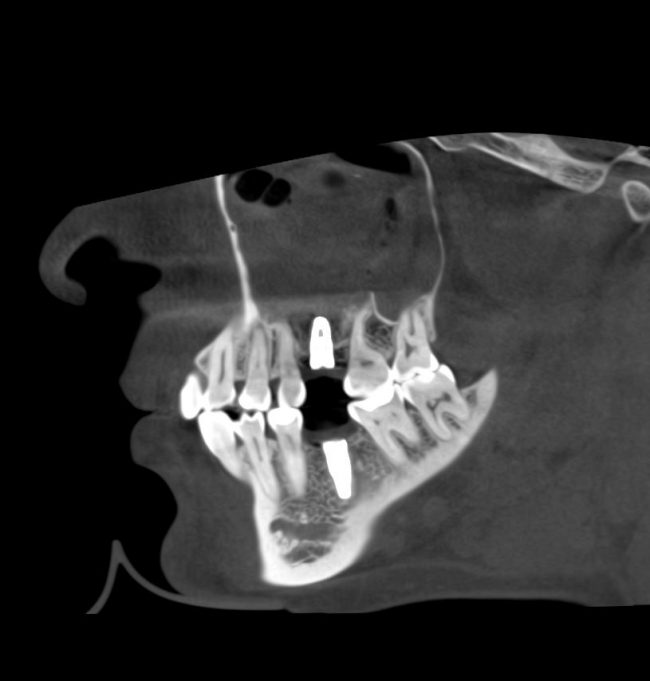

Для этого мы сделали КЛКТ:

И КЛКТ показала нам, что с имплантатами и окружающей костью всё зашибись. Через 12 лет после операции, отсутствия наблюдения, пофигизма в замене временных коронок! Нужны ли тебе еще какие-нибудь доводы в пользу долгосрочной эффективности метода?